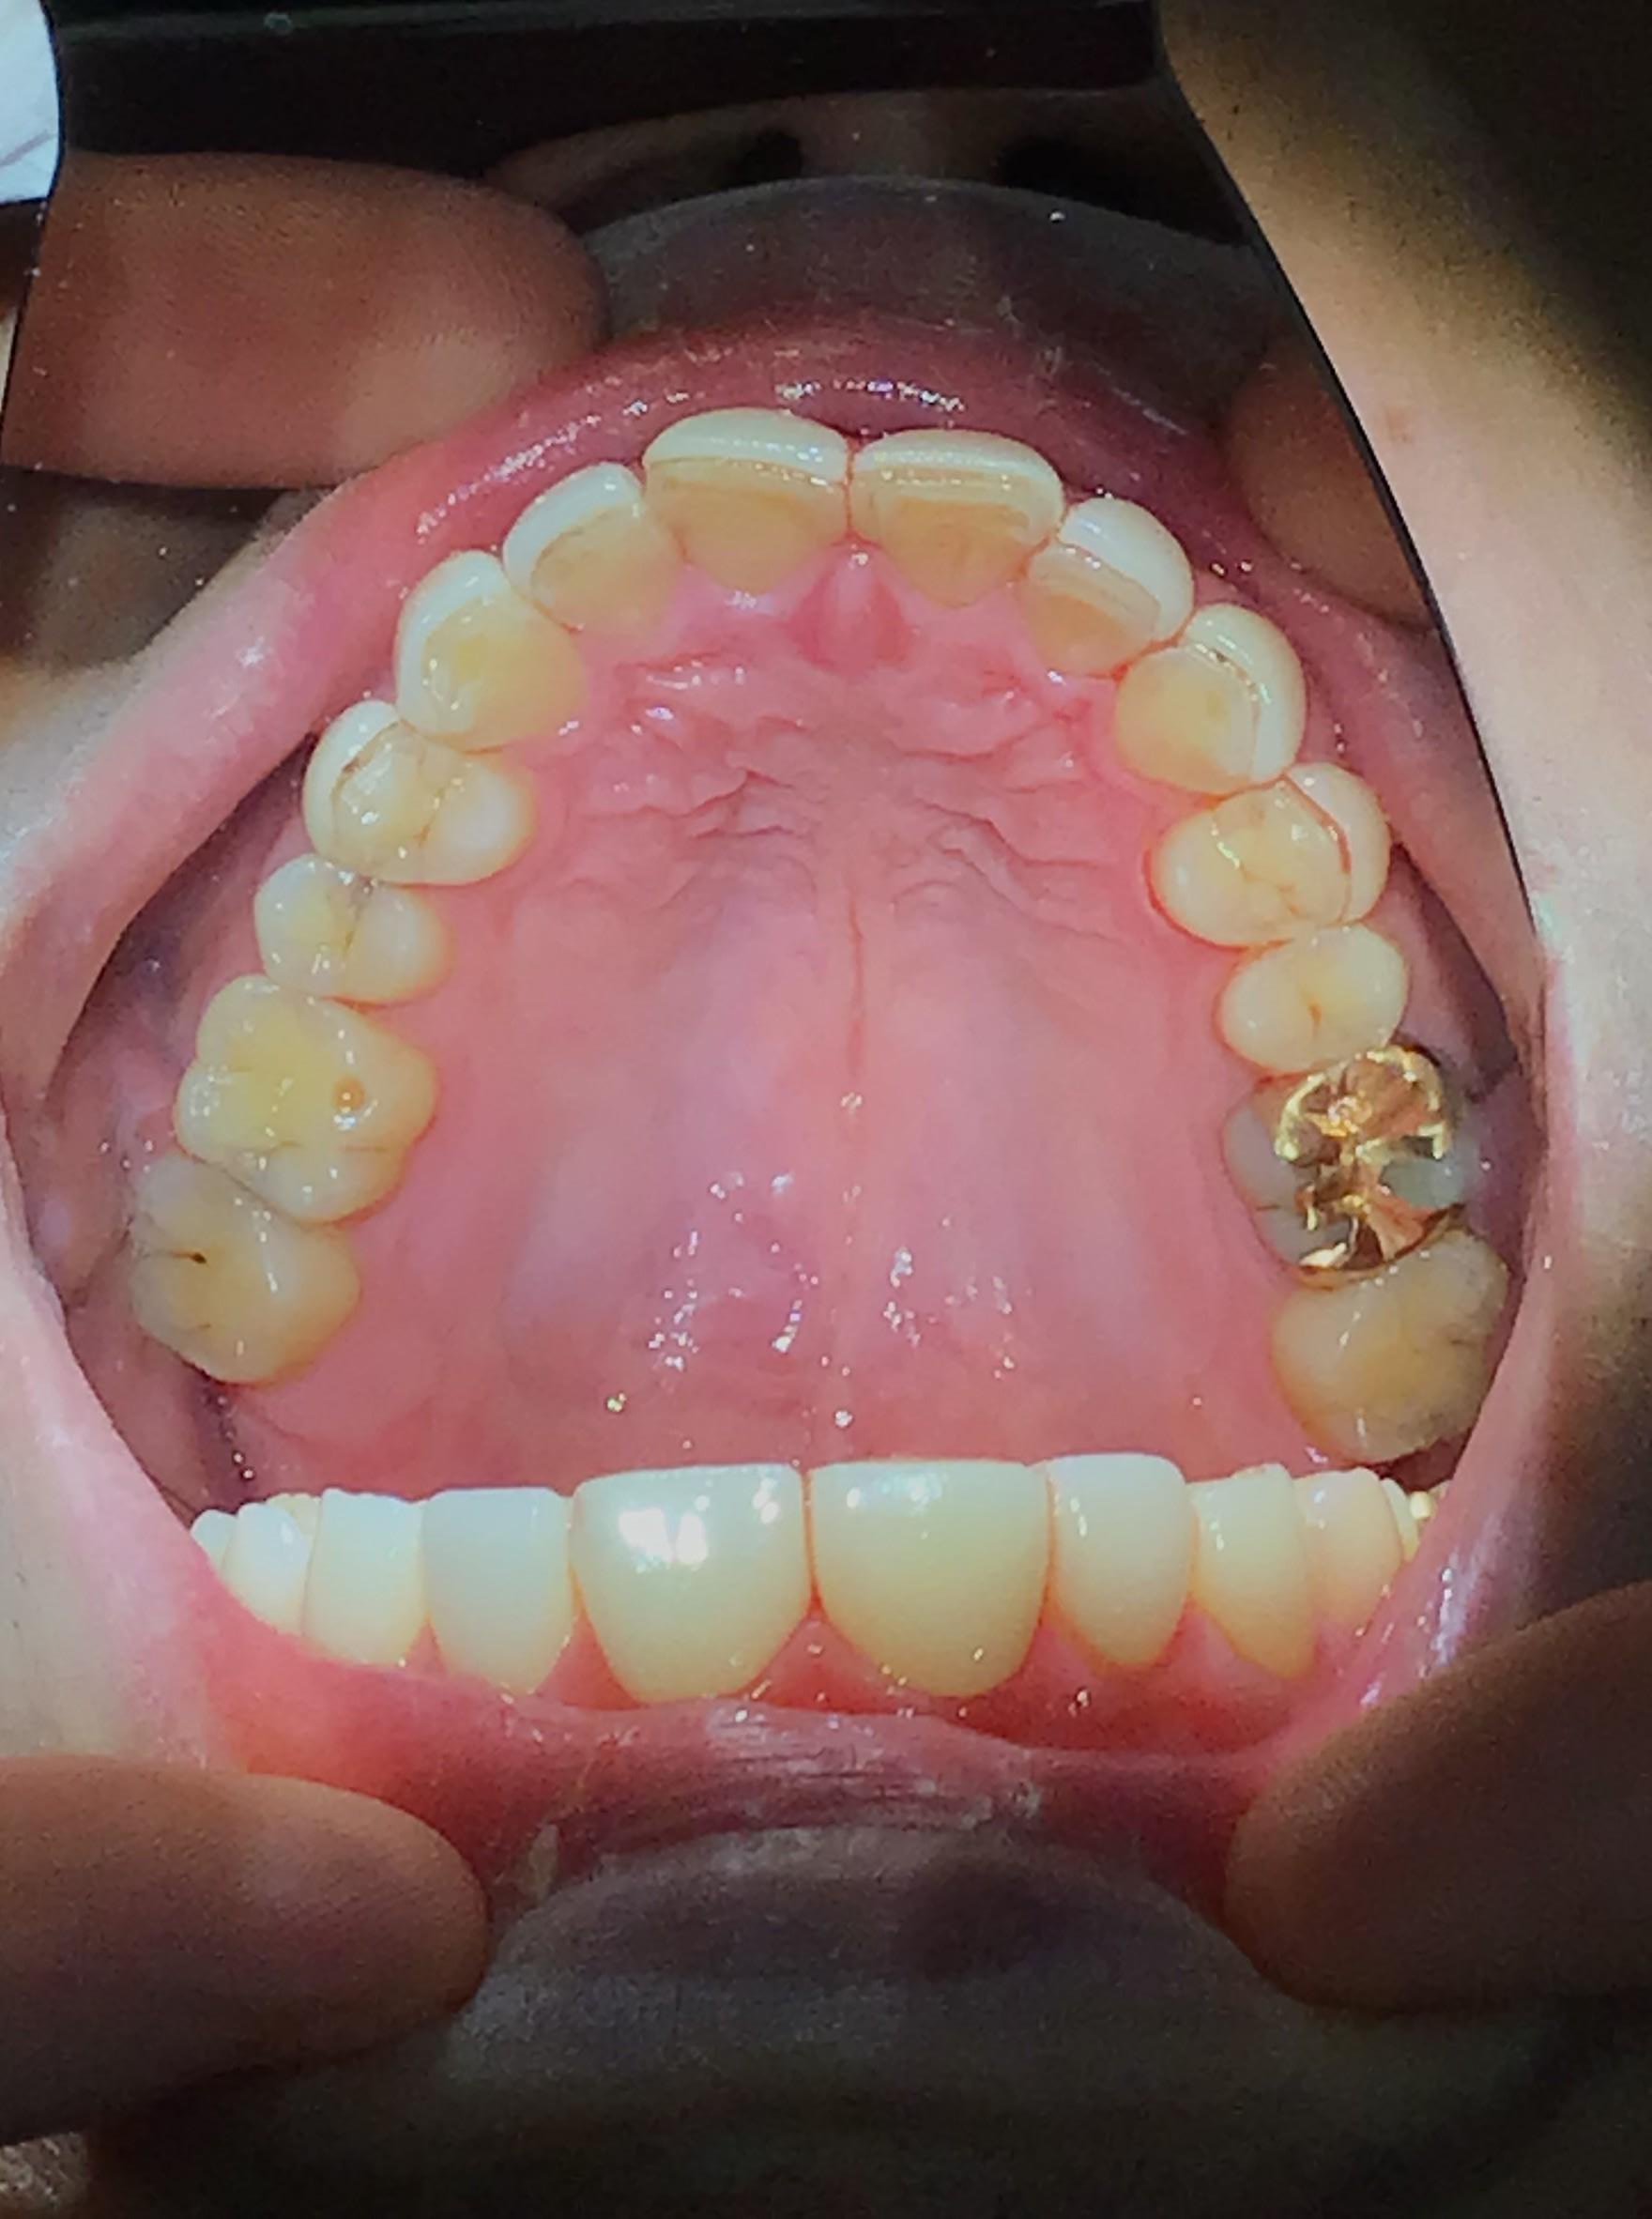

CASE 10

BEFORE

▶

AFTER

20代。 「前歯がデコボコしているのが気になる」「笑った時に歯並びが悪く見える」というお悩みでご来院。 仕事やプライベートで目立つワイヤー矯正は避けたいとのことで、透明なマウスピース矯正をご希望されました。